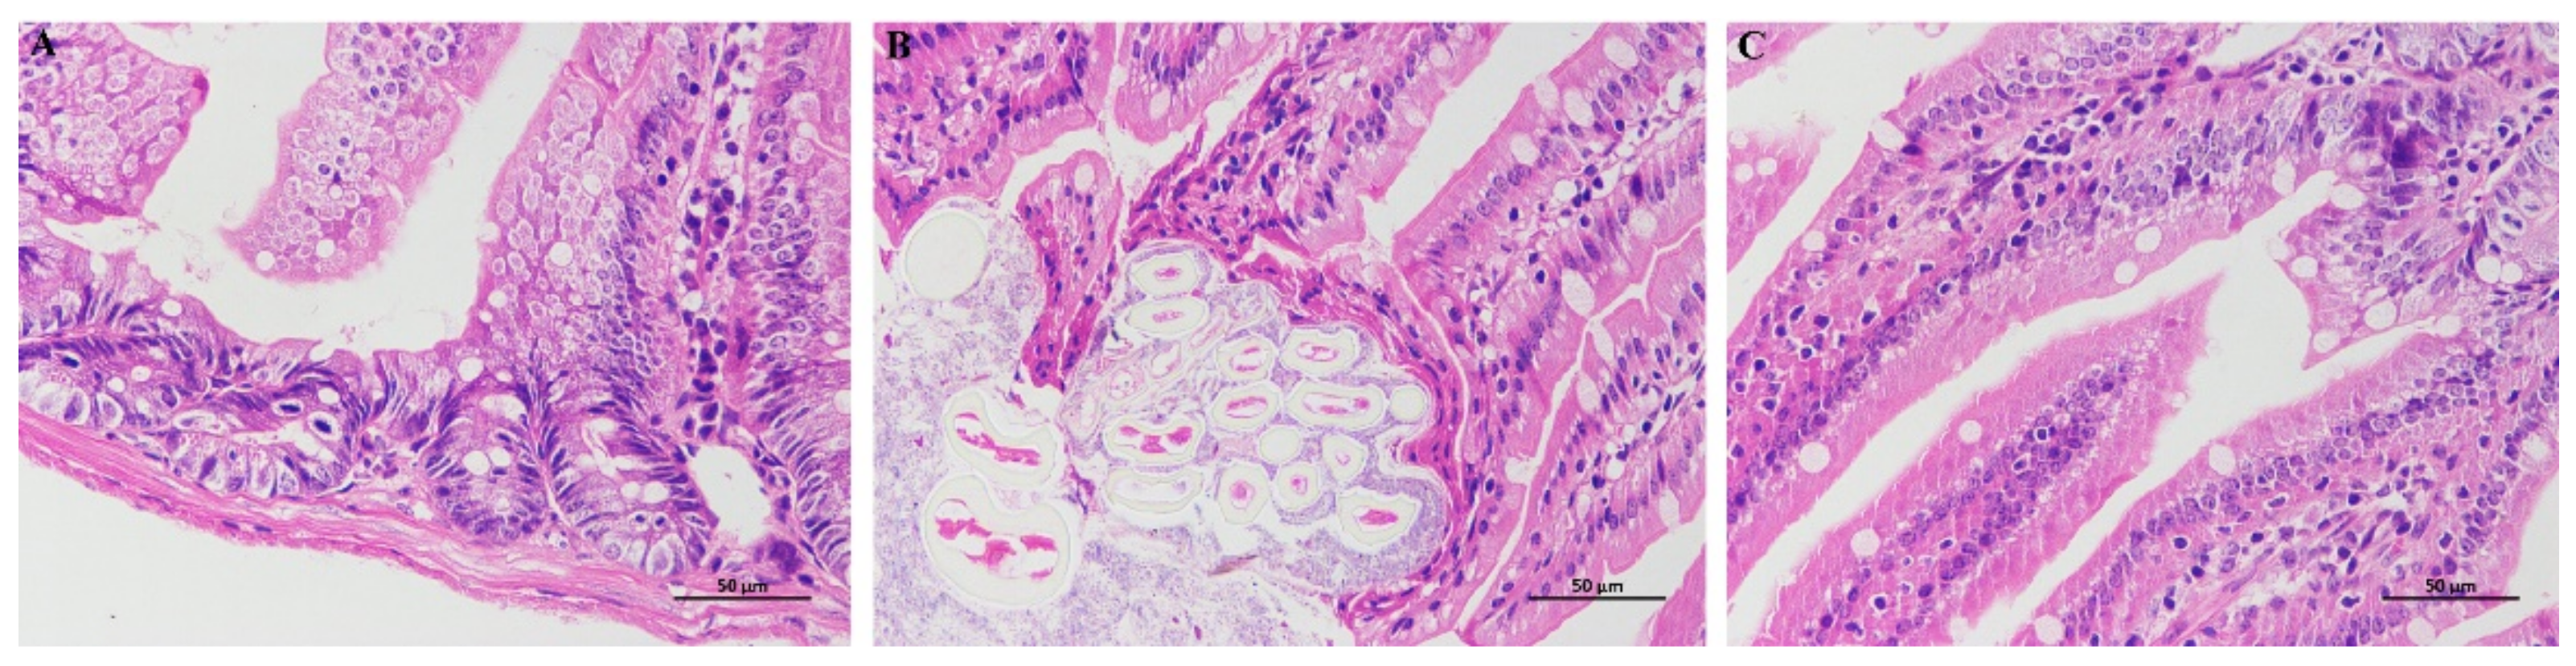

3.4. HE Staining